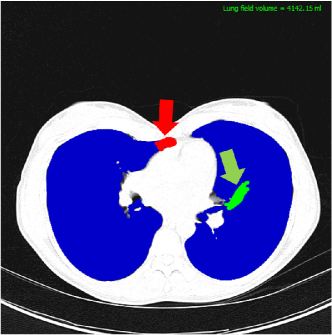

Refer to caption

Figure 5: Manual correction using the CIDI-Lung-Seg. The practitioner can add (green) or delete (red) the misclassified areas by stroke painting mechanism.

Once the initial lung regions are obtained, the annotation results are presented to the user. As shown in the results section, the initial results already provide a normal lung parenchyma for the target with the initial volume estimate. Any refinement (i.e., addition or deletion) in the initial boundaries can be easily incorporated by manual painting tool as shown in Fig. 5. Once the annotation is finalized it can be saved (ANALYZE 7.5 NifTI format) for subsequent analysis. The software currently supports NifTI format, more formats will be supported in the future releases of the software.